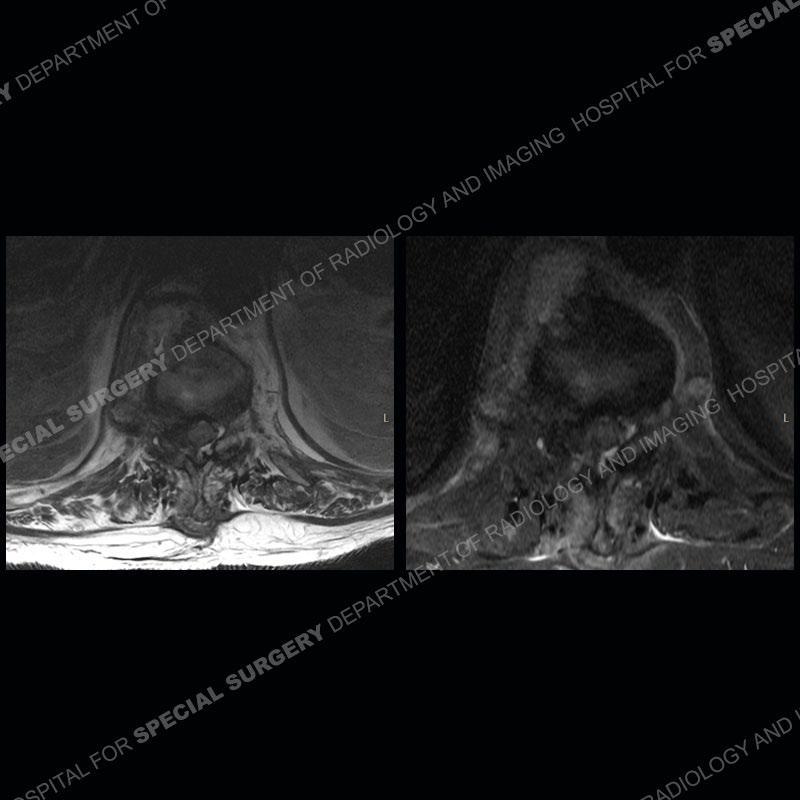

The initial MRI shows edema with a subtle fracture of the T11 vertebral body extending into the posterior elements. The subsequent MRI demonstrates a persistence and increased edema of the T11 body and posterior elements, anterior paraspinal edema/hematoma, and a progressive loss of the architecture of the T11 vertebrae. Seen well on the axial images of the MRI is the loss of CSF of the thecal sac/severe stenosis and severe right neural foraminal stenosis. The CT examination shows the loss of architecture of T11 from continued fracture and collapse. Well seen also is paravertebral osteophyte formation with bony bridging and bony bridging of the facet joints. There is an overall relative preservation of the disc spaces.

Diagnosis: DISH fragility fracture